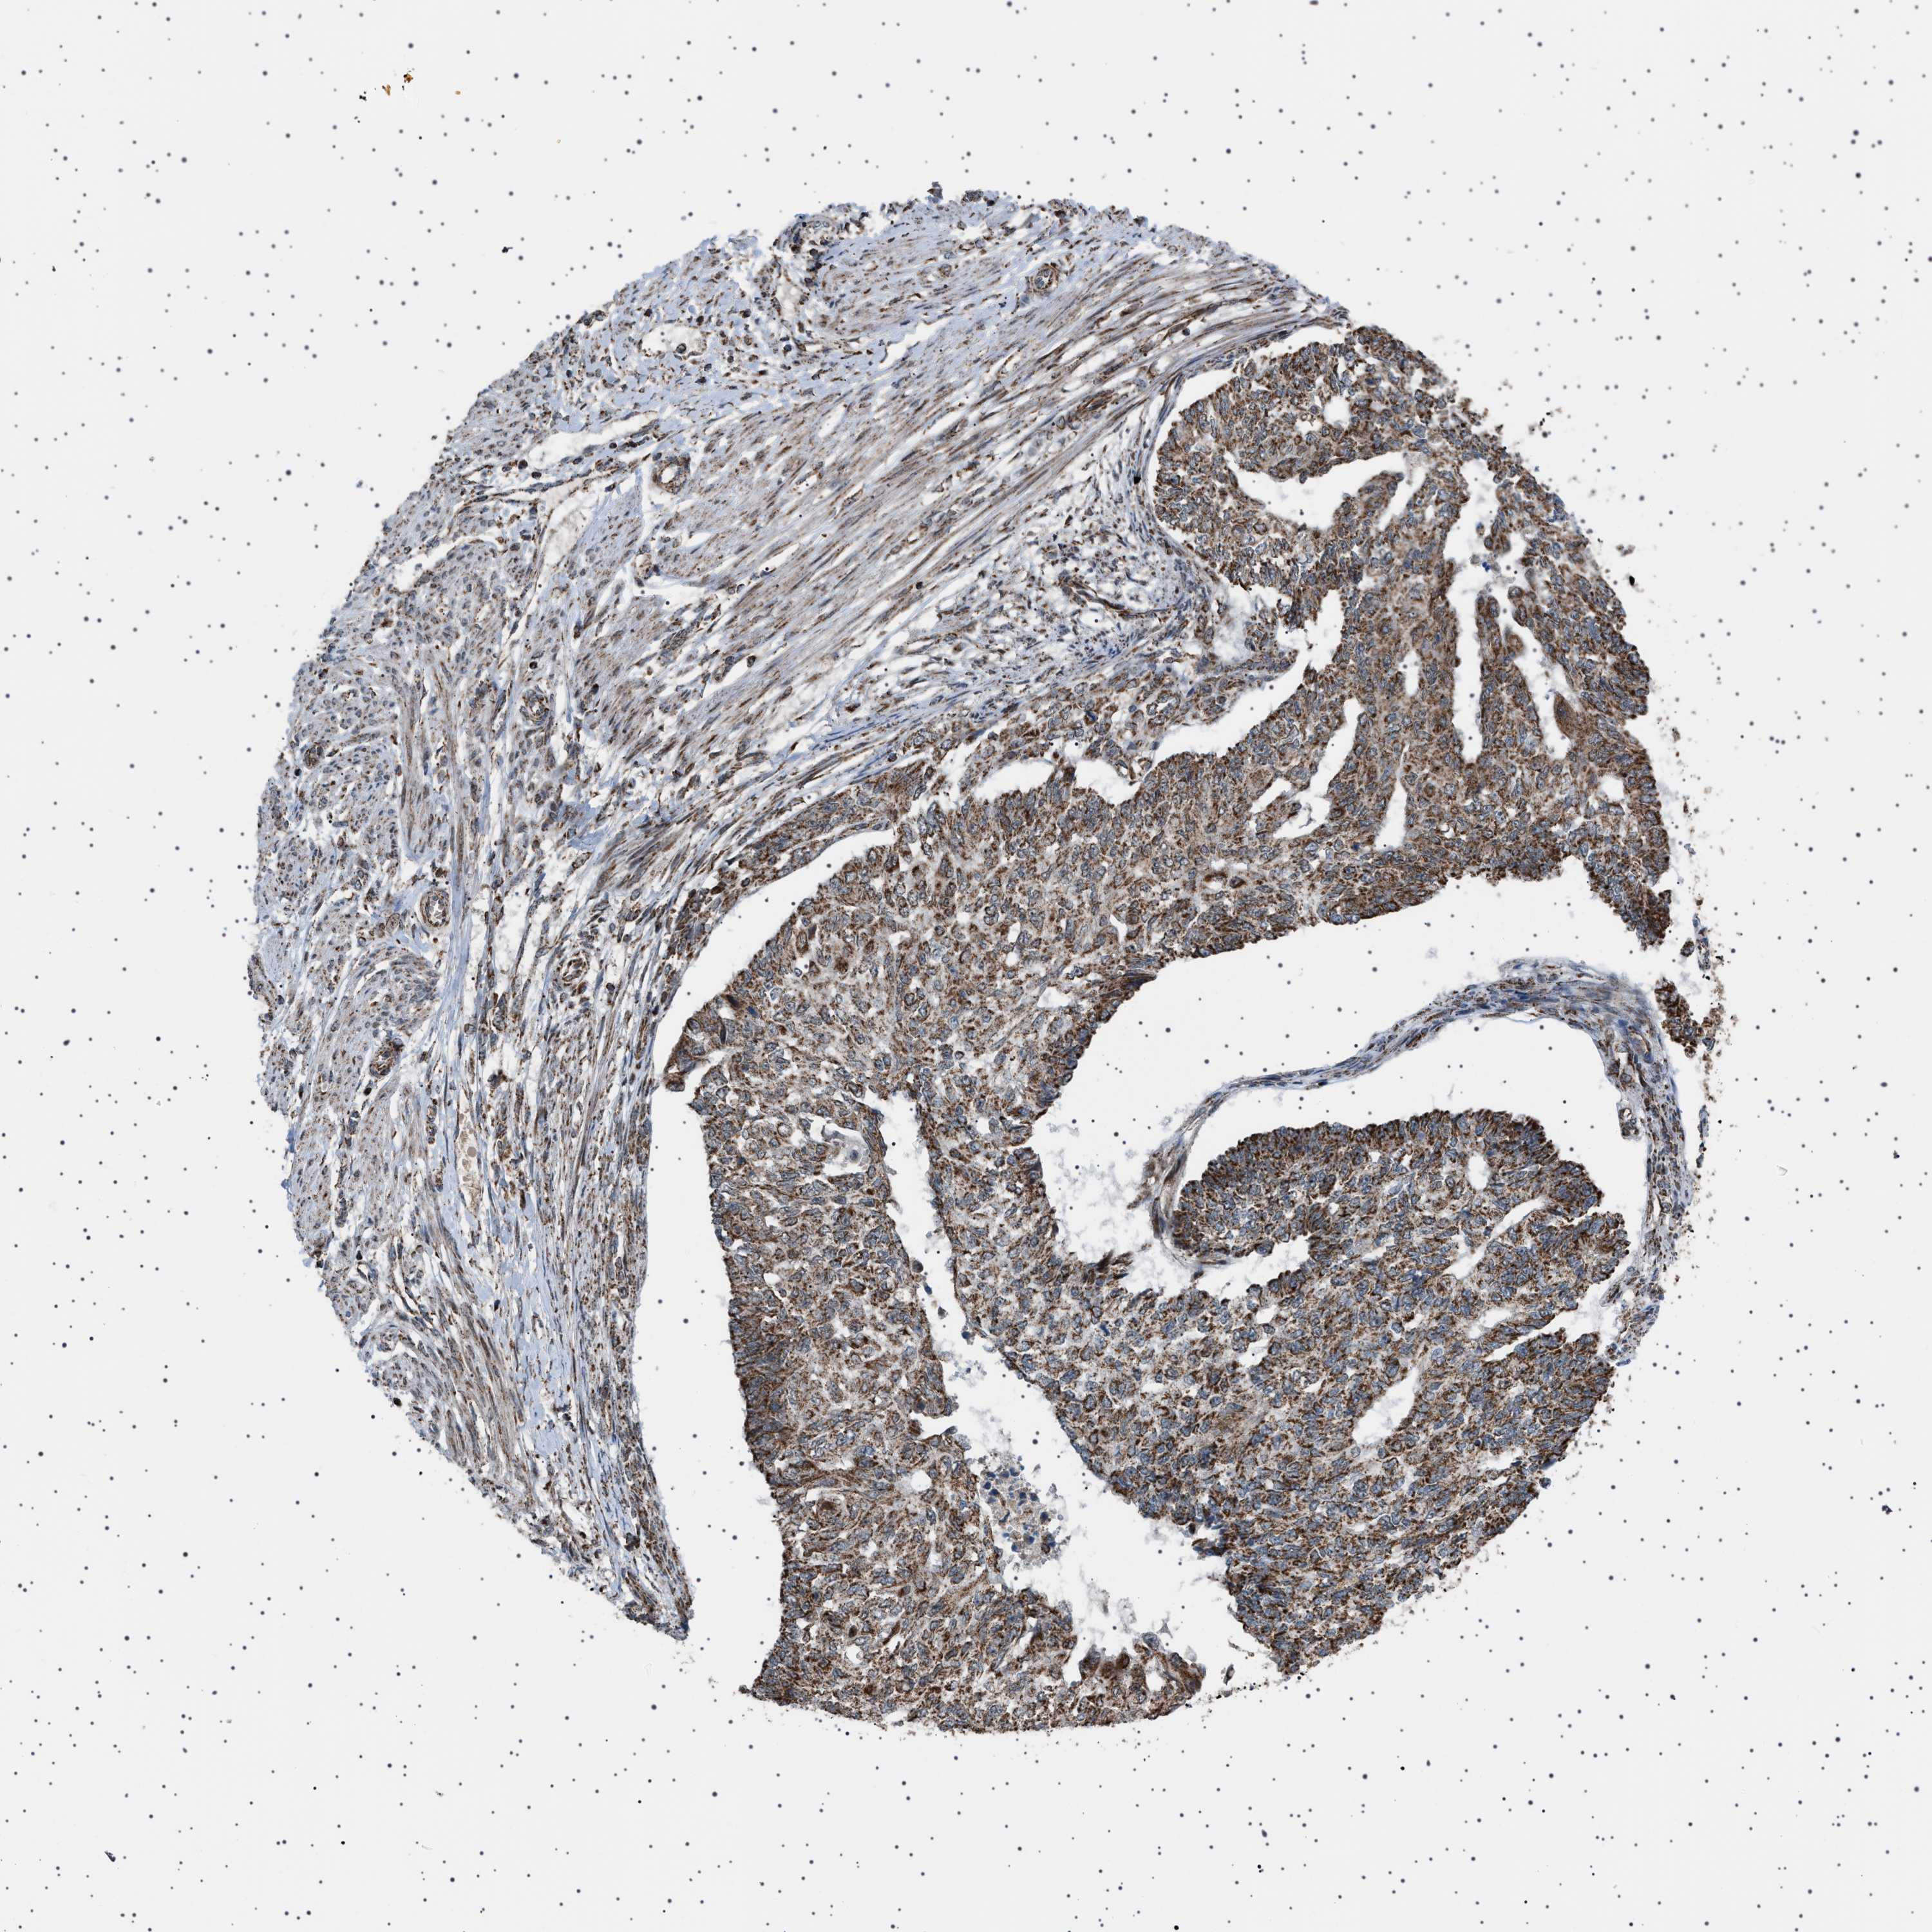

ENDOMETRIAL CANCER - Protein expressioni

A mouse-over function shows sample information and annotation data. Click on an image to view it in a full screen mode. Samples can be filtered based on level of antibody staining by selecting one or several of the following categories: high, medium, low and not detected. The assay and annotation is described here.

Note that samples used for immunohistochemistry by the Human Protein Atlas do not correspond to samples in the TCGA dataset.

Antibody stainingi

Antibody staining in the annotated cell types in the current human tissue is reported as not detected, low, medium, or high, based on conventional immunohistochemistry profiling in selected tissues. This score is based on the combination of the staining intensity and fraction of stained cells.

Each image is clickable and will lead to virtual microscopy that enables deeper exploration of all samples and also displays staining intensity scores, fraction scores and subcellular localization as well as patient and tissue information for each sample.

Antibody HPA017214

Staining

High

Medium

Low

Not detected

Intensity

Strong

Moderate

Weak

Negative

Quantity

>75%

75%-25%

<25%

None

Location

Nuclear

Cytoplasmic/membranous

Cytoplasmic/membranous,nuclear

Adenocarcinoma, NOS